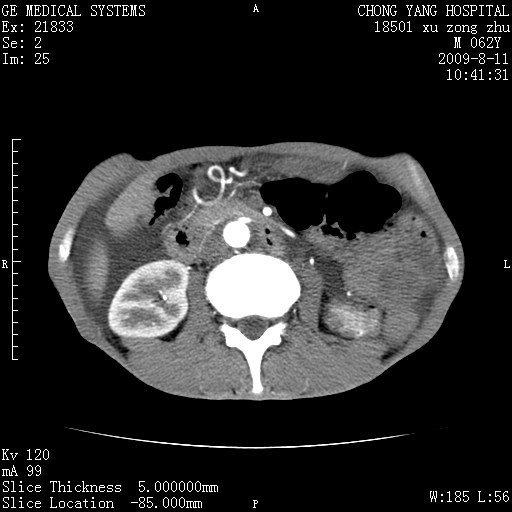

以下是引用杀毒软件在2009-8-11 16:35:00的发言:[br]肝内胆管扩张局限于左叶,胆管内有结石伴肝外胆管结石,胆管壁增厚呈弥漫性并发腹腔积液,胰腺边界模糊。[br][br]考虑---胆总管及肝内胆管结石继发胆管炎及胰腺炎,左肾下极囊肿,腹水。

以下是引用zjzjr在2009-8-11 17:35:00的发言:[br]肝内胆管扩张局限于左叶,胆管内有结石伴肝外胆管结石,胆管壁增厚呈弥漫性并发腹腔积液。[br][br]考虑---胆总管及肝内胆管结石继发胆管炎,左肾下极囊肿,腹水。